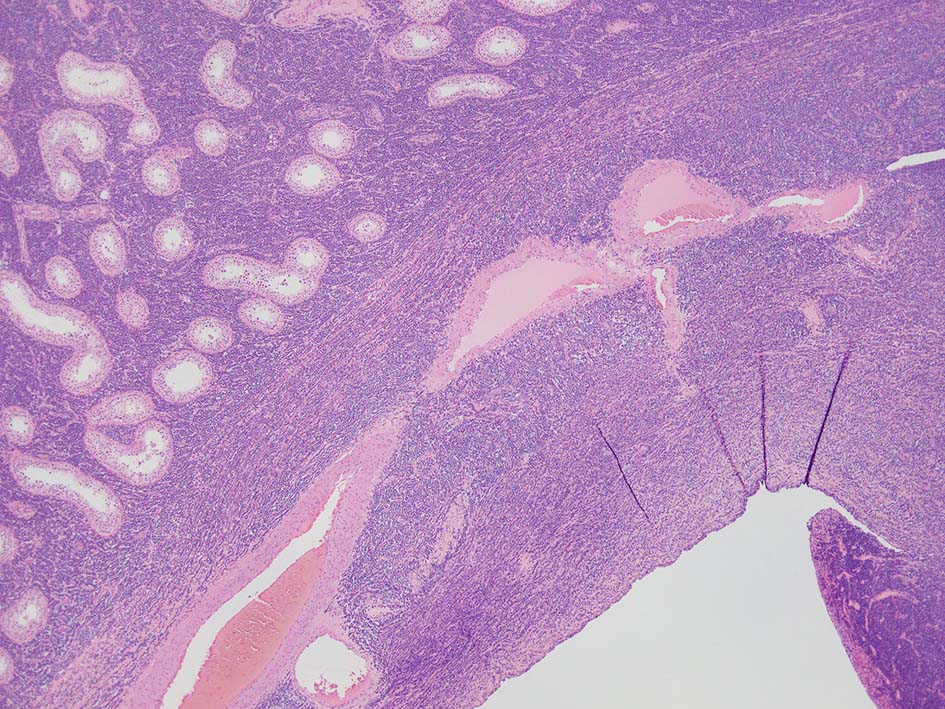

loupe像では, 腫瘍細胞が髄様密に浸潤増殖する部位と, 精細管をスペアするように管間に腫瘍細胞が浸潤する部分(右端図 A)がある.

切り出し図とは天地を逆にした右端図では, 髄様密な部分は白膜内で増殖するリンパ腫瘤(B)であることがわかる. 精巣上体の一部に浸潤がみられる(C)

loupe像Aの領域: 精細管をスペアするように, 小型リンパ球優位, 一部中型のlymphoid cellsがシート状密に浸潤増殖する. tubulesのほとんどにはlymphoid cellsが浸潤していないが, LELに似たようなlympho-tubular lesionが少数認められた. x400高倍率では, 増殖細胞は, 粗く, 凝集したクロマチンをもつ類円形, non-cleavedな核をもつ細胞質の乏しいlymphoid cellsである. 核小体か凝集したクロマチンかわかりにくい.

精巣上体, 精巣周囲脂肪織への浸潤, 精巣実質, 白膜の非浸潤部